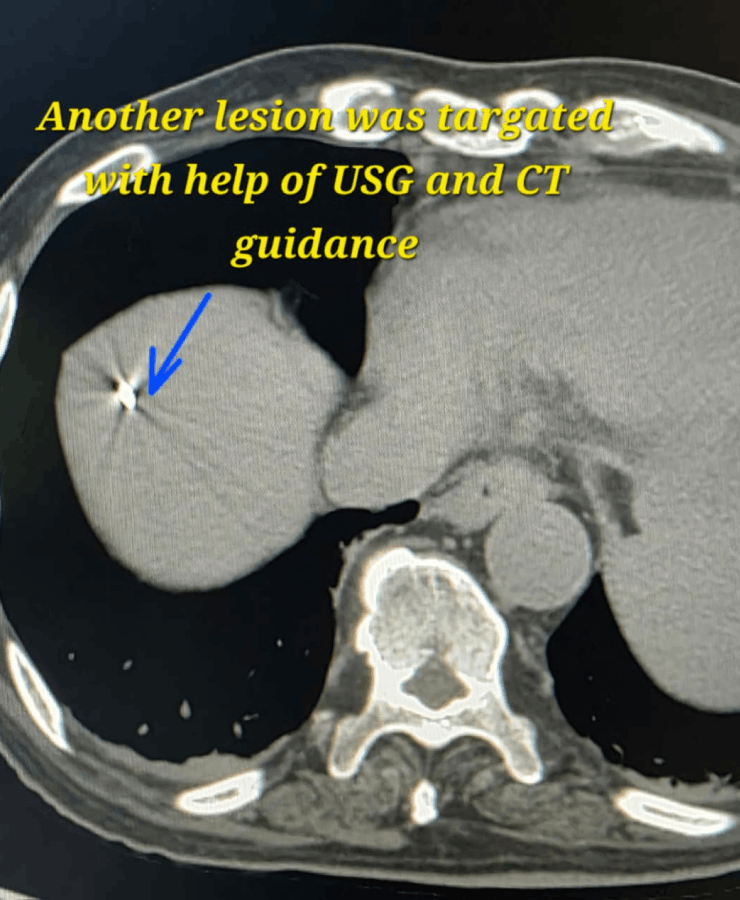

Microwave ablation of liver cancers

Kidney cancer treatment by Microwave Ablation method

- Procedures are performed under USG/CT guidance to precisely target the lesion while preserving as much normal kidney tissue as possible.